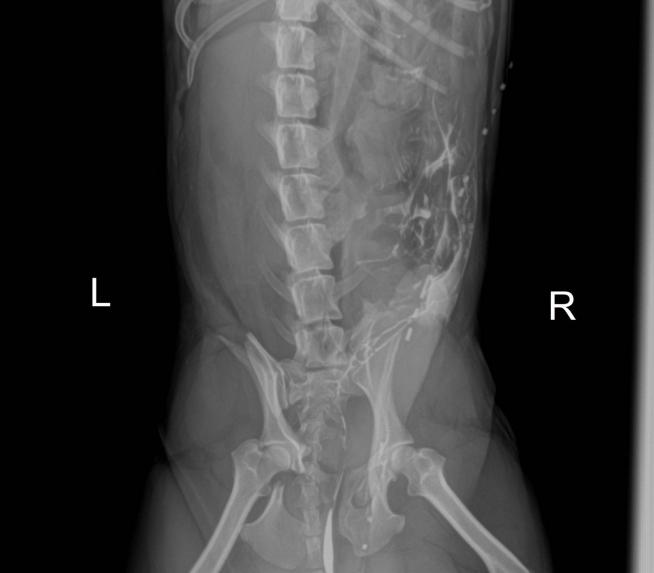

由于精神状态和生命体征暂时比较稳定,但动物较为疼痛,固止疼镇静处理,体格检查后可见后腹部腹侧阴茎两侧大面积皮肤损伤,淤血,有少部分溃烂,双后肢内侧均有皮肤溃烂,神经学检查未见明显异常,进行骨盆和腹部X光片检查,检查结果显示左侧髂骨体骨折,坐骨骨折,耻骨骨折,右侧荐髂关节骨折,另外可见腹部膀胱影像不明显,考虑到是后腹部车祸伤,有可能会导致膀胱破裂,对其进行膀胱造影,造影剂显示弥散性散开膀胱破裂。

3.3荐髂关节脱位整复固定:将犬置于塑性垫上右侧卧保定,皮肤切口向前始于髂背侧前棘,继续向后与其中线平行延伸至接近髋关节,沿切口线切开皮下组织,臀筋膜和脂肪,行髂骨背侧手术通路钝性分离臀中肌和荐棘肌,显露错位的荐髂关节,将髂骨外翻,触摸髂骨内侧骨凸出处,2.0钻头于髂骨内侧面骨凸出处钻孔,1.5钻头于荐椎耳状面背内侧钻孔,丝锥攻丝,将髂骨复位,放置2.0mmx20mm螺钉固定,之后从螺钉背侧打入1.5mm髓内针固定,剪除多余髓内针。3/0Monosyn依次缝合臀中肌和荐棘肌、臀筋膜、皮下组织和皮肤。